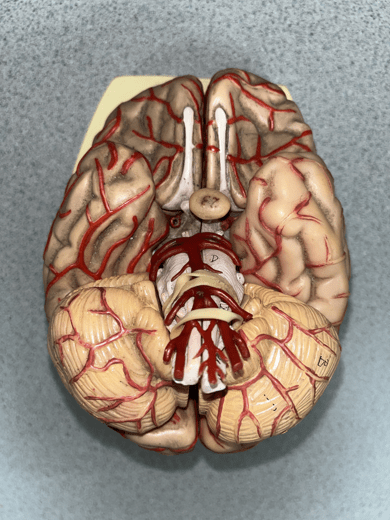

anterior cerebral artery

• An artery of the cerebral circulation.

• Originates from the internal carotid artery.

• Supplies the frontal and parietal lobes of the brain.

• Originates from the internal carotid artery.

• Supplies the frontal and parietal lobes of the brain.

posterior communicating artery

• An artery of the cerebral circulation (not shown).

• Connects the posterior cerebral and internal carotid arteries.

• Connects the posterior cerebral and internal carotid arteries.

posterior cerebral artery

• An artery of the cerebral circulation.

• Originates from the basilar artery.

• Supplies the temporal and occipital lobes, midbrain, and thalamus.

• Originates from the basilar artery.

• Supplies the temporal and occipital lobes, midbrain, and thalamus.

middle cerebral artery

• An artery of the cerebral circulation (not shown).

• Originates from the internal carotid arteries.

• Supplies the frontal, temporal, and parietal lobes.

• Originates from the internal carotid arteries.

• Supplies the frontal, temporal, and parietal lobes.

basilar artery

• An artery of the cerebral circulation.

• Originates from the convergence of the vertebral arteries.

• Supplies the cerebellum, pons, and inner ear through its branches.

• Originates from the convergence of the vertebral arteries.

• Supplies the cerebellum, pons, and inner ear through its branches.